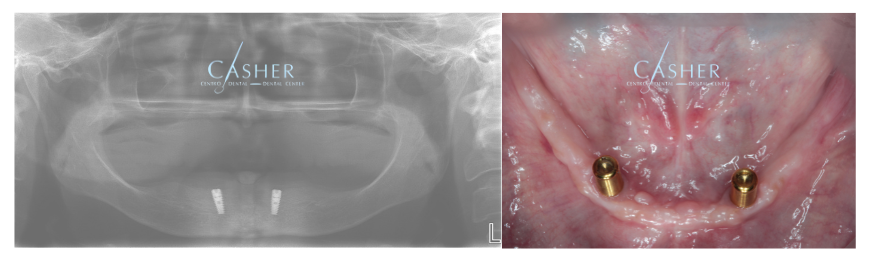

El caso clínico: paso a paso

Nuestro paciente llegó buscando una alternativa a la prótesis tradicional. Le realizamos una planificación con diagnóstico digital y colocamos dos implantes inferiores, preparados para el sistema Locator. A continuación te mostramos algunas imágenes del proceso:

- Implantes colocados en mandíbula inferior, perfectamente integrados.

- Adaptación de la prótesis superior existente.

- Prueba y ajuste del sistema Locator.

- Resultado final: prótesis inferior estable, cómoda y estética.

- El resultado no solo fue funcional: la paciente volvió a sonreír con seguridad.